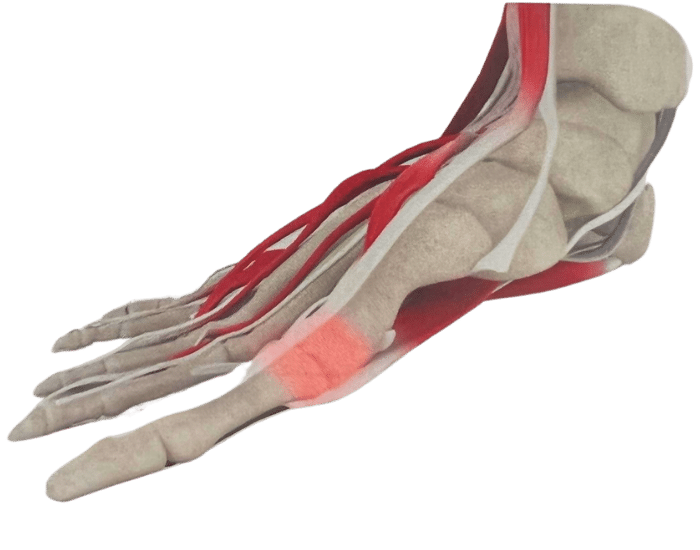

There are numerous reasons why you might need Custom Foot Orthotics. If you have pain in your foot, heel, knee or hip, have high arches or flat feet; or just being regularly on your feet and are getting any aches or pains in the feet or legs, or suffering from general foot pain while walking, running, playing sports or even at rest you qualify for Custom Foot Orthotics.